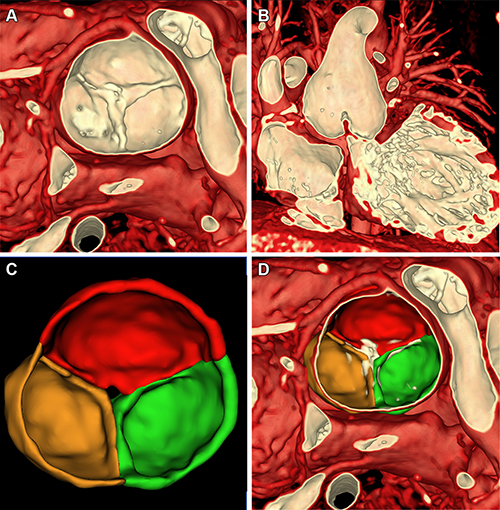

Figure 5. Volume rendering of multiphase steady-state imaging with contrast enhancement (ie, MUSIC) from ferumoxytol-enhanced cardiac MRI in a 4-year-old male patient with severe aortic insufficiency (patient 1) to inform valve repair. (A) Axial multiplane reconstruction in diastole. (B) Volume rendering from axial view in diastole. (C) Axial multiplane reconstruction in systole. (D) Axial view of volume-rendered image with cutting plane through aortic valve in systole.